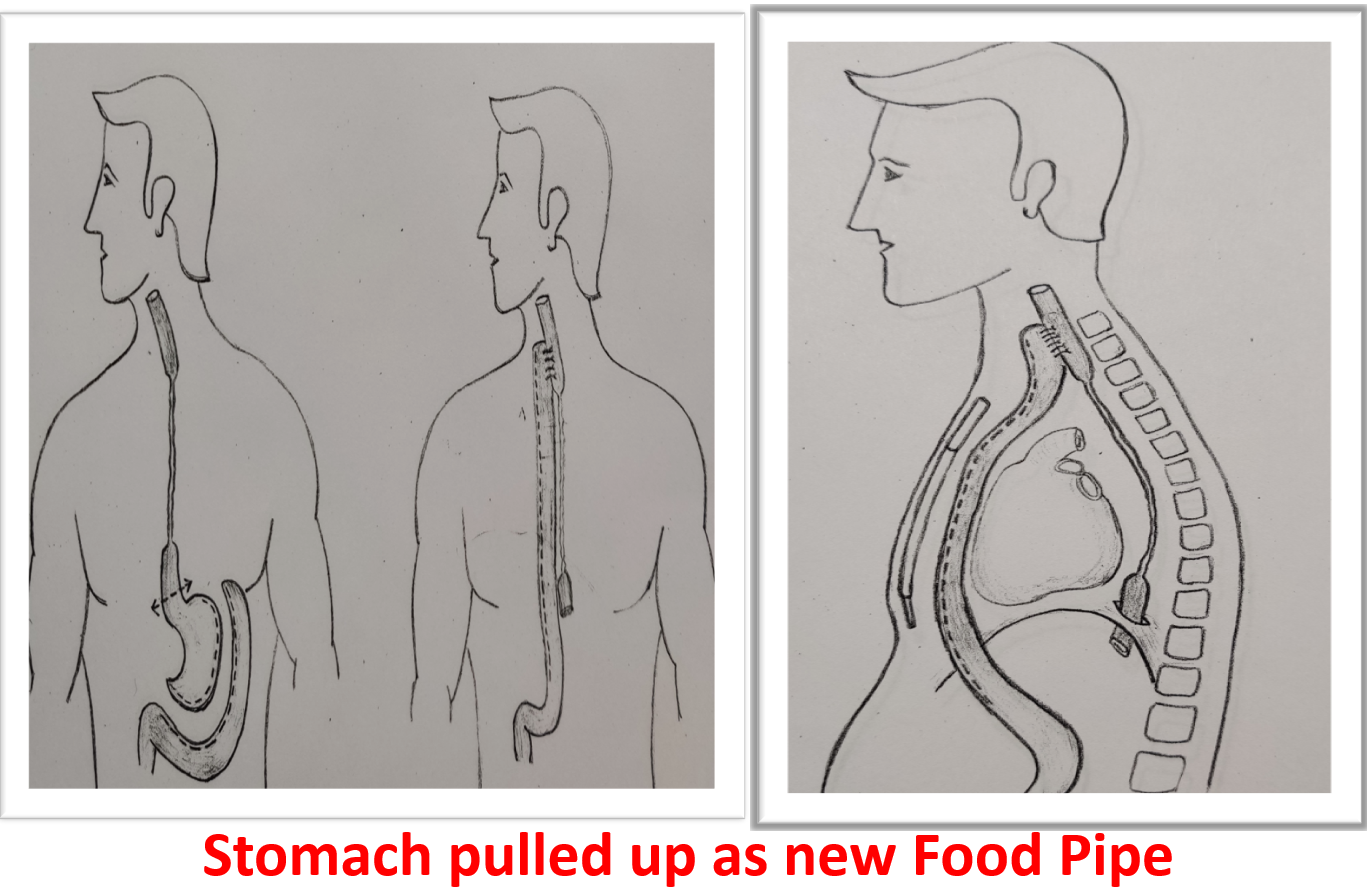

The treatment initially is to dilate the stricture with endoscope to restore eating which might be successful in some. Failing endoscopic dilatation or stricture which has ruptured during dilation need surgical replacement. Surgical replacement has evolved from using artificial pipes to bodies own organs suitable to restore the food pipe. The surgical principle is to identify the healthy upper part of esophagus which is in the neck, leave behind or remove the scarred esophagus, prepare the conduit (stomach tube, colon, jejunum) for replacement, transport it from abdomen to the neck under the chest bone (sternum) and join it to healthy esophagus in neck (Fig- 2/2p/3). The entire procedure involves three major compartments of human body, lasts from 4 to 8 hours, more than a week to recover from surgery and with known procedure related morbidity and mortality if not performed in a specialized centre. Patient are allowed to sip liquids from firs day to resume to normal diet may take a week but eventually they “EAT”